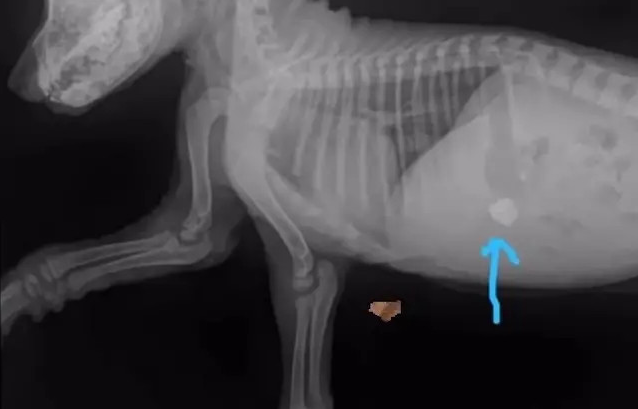

Krista — osoba o wielkim sercu — niezwłocznie zabrała Aylę do kliniki weterynaryjnej. Diagnoza ujawniła poważne zaburzenia: kości tylnych kończyn były zdeformowane z powodu silnego niedoboru wapnia, a suczka, by zaspokoić głód, żuła kamyki. Mimo tego zatrważającego obrazu, specjaliści znaleźli drobną iskrę optymizmu — brak złamań dawał szansę na powrót do zdrowia.

Już po dwóch dobach leczenia nadeszły kolejne pozytywne wieści. Wyniki badań krwi wskazały, że poza ciężką świerzbowością i niedoborami pokarmowymi, nie stwierdzono innych poważnych schorzeń. Zastosowano miękki opatrunek podtrzymujący kończyny i rozpoczęto podawanie preparatów wapniowych — to pozwoliło Aylce zrobić pierwsze, niepewne kroki ku sprawności. Przywrócenie radości życia wspomogła także prosta zabawka; mała piłeczka natychmiast wywołała merdanie ogonem.